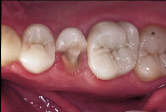

| Figure 2: Post-operative view of the restored fractured distal incisal edge of the right central incisor done without any mechanical tooth preparation. |

Consider, for example, the common occurrence of a fractured incisal edge in a newly erupted central incisor of a child patient. Traditionally, the perimeter of the fractured tooth substance is chamfered to accommodate an increase in the bondable substrate area and to allow for an imperceptible tooth restoration. In many instances, the preparatory procedure removes more sound tooth structure than the initial trauma. This irreversible tooth preparation will affect all future restorative interventions. In the case of the eight-year-old patient depicted in Fig. 2, restoration of the distal incisal edge of the right central incisor was done without the use of any mechanical tooth preparation. The slightly compromised esthetic result (shown 18 months after a second traumatic episode fractured the adjacent lateral incisor) was counterbalanced by the fact that the restoration was done without further loss of sound tooth substance. The restoration should last approximately five years, at which point an improved restorative material will allow for an enhanced esthetic result. This case is illustrative of an evolving restorative mentality that acknowledges: